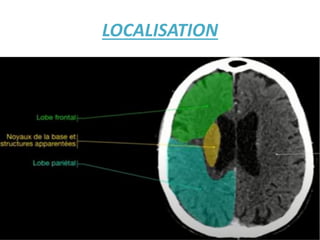

comment je peux faire la différence

entre lobe frontal et pariétal ??

Les 2 hémisphères cérébraux sont séparés

par la faux du cerveau. La scissure

centrale/Du rolando dessine un oméga

concave en avant. Cettes cissure est

capitale car en avant se trouve la

circonvolution frontale

ascendante/motrice. En arrière se trouve la

circonvolution pariétale

ascendante/sensitive

LOCALISATION